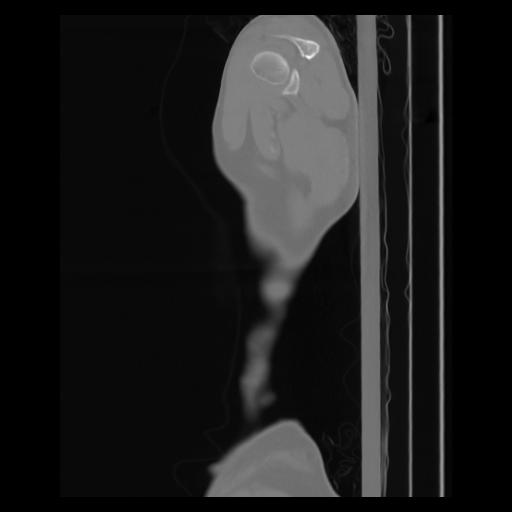

30 CUERPO,CE,Sagittal,3.000,CUERPO,Sagittal,